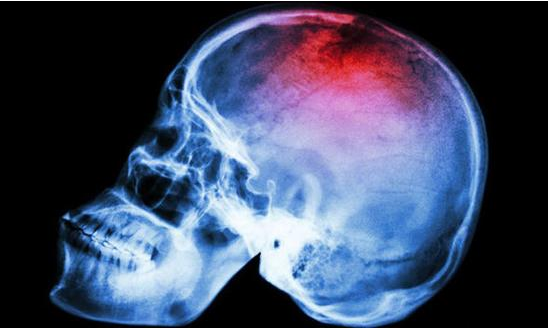

Canavero 博士也声称,接到许多英国志愿者的申请信息。他声称手术的第一步将是冰冻大脑和身体,阻止脑细胞死亡。然后切开脖子,将关键的动脉和静脉将连接到管子上。在进行移植之前将切断患者的脊椎。

当肌肉和血液供给成功连接之后,病人将昏迷一个月时间来限制新移植头颅的活动,同时将通过电刺激让脊椎新连接得到强化。这位野心勃勃的医生相信,物理疗法将让接受头部移植手术的病人在一年内下床走路。